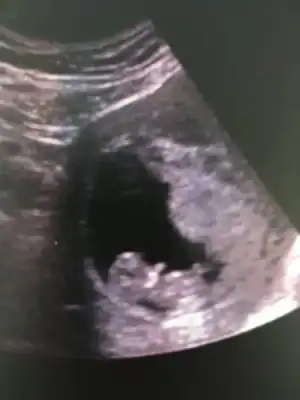

Burda 9 haftalikti. Yorumlarsaniz cok seviniirm :)